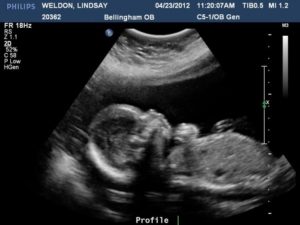

Ультразвуковое исследование в таком сроке обычно проводится в рамках второго скрининга. УЗИ на 20 неделе беременности может понадобиться для оценки протекания беременности, определения пола ребенка, вероятности пороков развития и хромосомных аномалий.

Также УЗИ на 20 неделе беременности позволяет определить, соответствует ли размер плода сроку беременности, в норме ли состояние околоплодных вод и плаценты. При проведении УЗИ на 20 неделе беременности изучаются и внутренние органы крохи: почки, желудок, мочевой и желчный пузырь, печень, легкие, кишечник.

Также подлежит тщательному исследованию и сердце малыша – если обнаруживается какое-то несоответствие, понадобится специализированное ультразвуковое исследование сердца. К сожалению, пороки сердца являются сегодня одним из наиболее распространенных пороков развития плода.

Кроме того, что ультразвук поможет оценить, соответствует ли норме развитие малыша, УЗИ на 20 неделе беременности к тому же покажет: малыш в утробе матери активно растет и развивается. А еще – вовсе не скучает, ведь размеры его позволяют еще пока свободно двигаться у мамы в животике, чем ребеночек активно пользуется, переворачиваясь и кувыркаясь.

Расшифровка УЗИ 20 недель беременности необходима для оценки протекания вашей беременности, состояния околоплодных вод, установления пола малыша, исключения хромосомных аномалий и пороков развития.

Также, в 20 недель беременности фото УЗИ позволит определить соответствие размера ребенка сроку беременности. На УЗИ изучаются внутренние органы малыша, тщательно обследуется его сердце.

А еще, во время ультразвукового исследования, вы можете попросить доктора сделать на сроке 20 недель беременности фото плода.